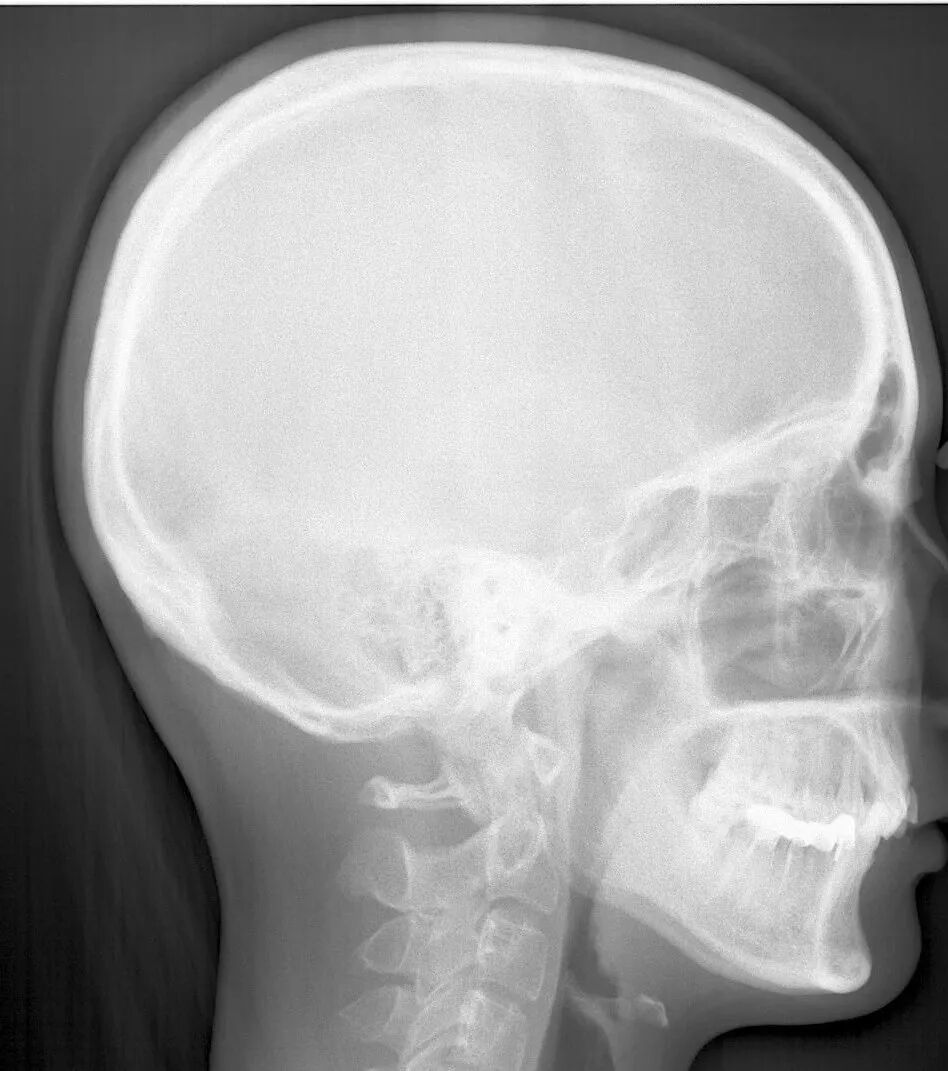

头侧片:可以了解骨量与牙齿的关系,判断正畸是否需要拔牙;判断错颌类型:牙性or骨性;判断侧貌类型:凸面型/凹面型/直面型。